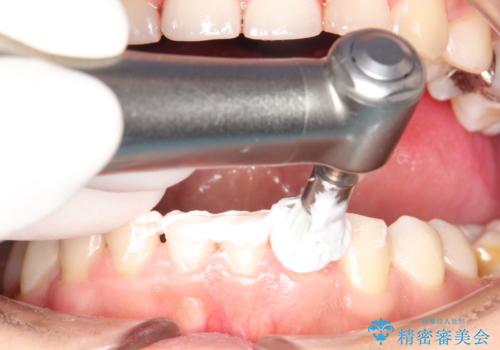

治療途中

かなり久しぶりの歯科医院との事で、全体的に古くからの歯垢・歯石が多く付着していたため、自費クリーニング(PMTC)60分コース・歯周ポケット検査(保険適応)を行いました。